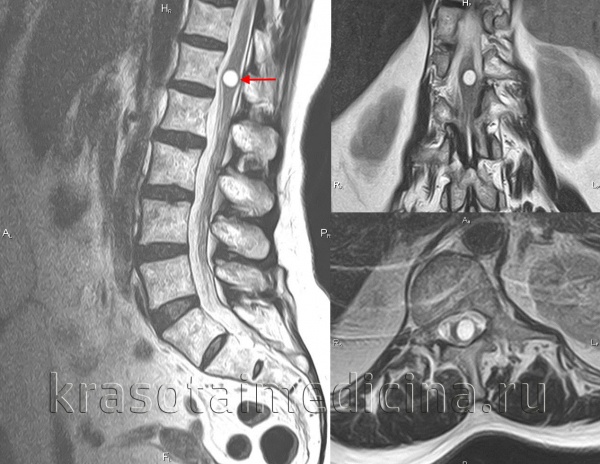

- МРТ спинного мозга. Исследование признано «золотым стандартом» обследования больных с подозрением на гидромиелию. По данным МРТ-снимков выявляются центральные полости размером от 2 мм до 25 мм, увеличение поперечника спинного мозга, сдавление нервных корешков. Для уточнения причины делают МРТ головы, позвоночника.

- МРТ головного мозга. При нейровизуализации удается установить наличие, размеры, локализацию патологической полости в мозговом стволе. Для оценки движения цереброспинальной жидкости, исследования функционального состояния полости применяется методика PC-cine МРТ.

- МРТ спинного мозга. Поскольку сирингобульбия нередко возникает как осложнение прогрессирующей сирингомиелии, визуализации спинального канала необходима для поиска полостей в спинномозговом веществе. Для уточнения диагноза выполняется КТ шейного отела позвоночника, миелография.

Сирингомиелия

Сирингомиелия (от греческого «syrinx» - пустая дудка и «myelon» - спинной мозг) - хроническое заболевание центральной нервной системы, при котором в веществе спинного мозга, а иногда и в продолговатом мозге образуются полости. Истинная сирингомиелия связана с патологией глиальной ткани, в других случаях заболевание является следствием аномалий кранио-вертебрального перехода. Применение МРТ позвоночника значительно облегчило диагностику сирингомиелии. В случаях невозможности проведения МРТ визуализировать сирингомиелитические полости можно при помощи миелографии. Сирингомиелия не излечима, начавшись в молодом возрасте, она сопровождает больного всю жизнь. Пациентам проводится симптоматическая и нейропротекторная терапия, в тяжелых случаях - хирургическое дренирование полостей.

Рентгенологические методы диагностики могут выявить трофические проявления сирингомиелии в виде остеопороза, разрушения костных элементов сустава и т. п. Точно диагностировать сирингомиелию позволяет МРТ позвоночника, а при невозможности ее проведения - миелография. Эти методы обследования дают возможность увидеть сирингомиелические полости в спинном мозге и стволе.

Трофические язвы в сочетание с вазомоторными расстройствами на кистях рук и верхних конечностях указывают на потерю болевой чувствительности. КТ с внутривенным введением нутризамида выявляет увеличение спинного мозга в области локализации сирингомиелической полости; отсроченные снимки демонстрируют накопление в полости контрастного вещества. Методом выбора для диагностики сирингомиелии служит МРТ. Лечение хирургическое и зависит от локализации и причины сирингомиелии.